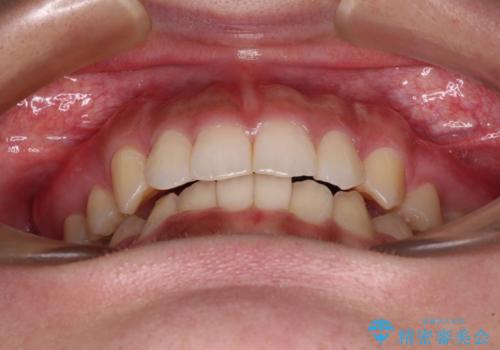

ワイヤー装置を用いた場合、一般的には2年程度で終了することを考えると、「移動量が多くなると治療期間が長くなる」というインビザライン矯正の最大の弱点が現れた治療となりました。

- 4年3ヶ月